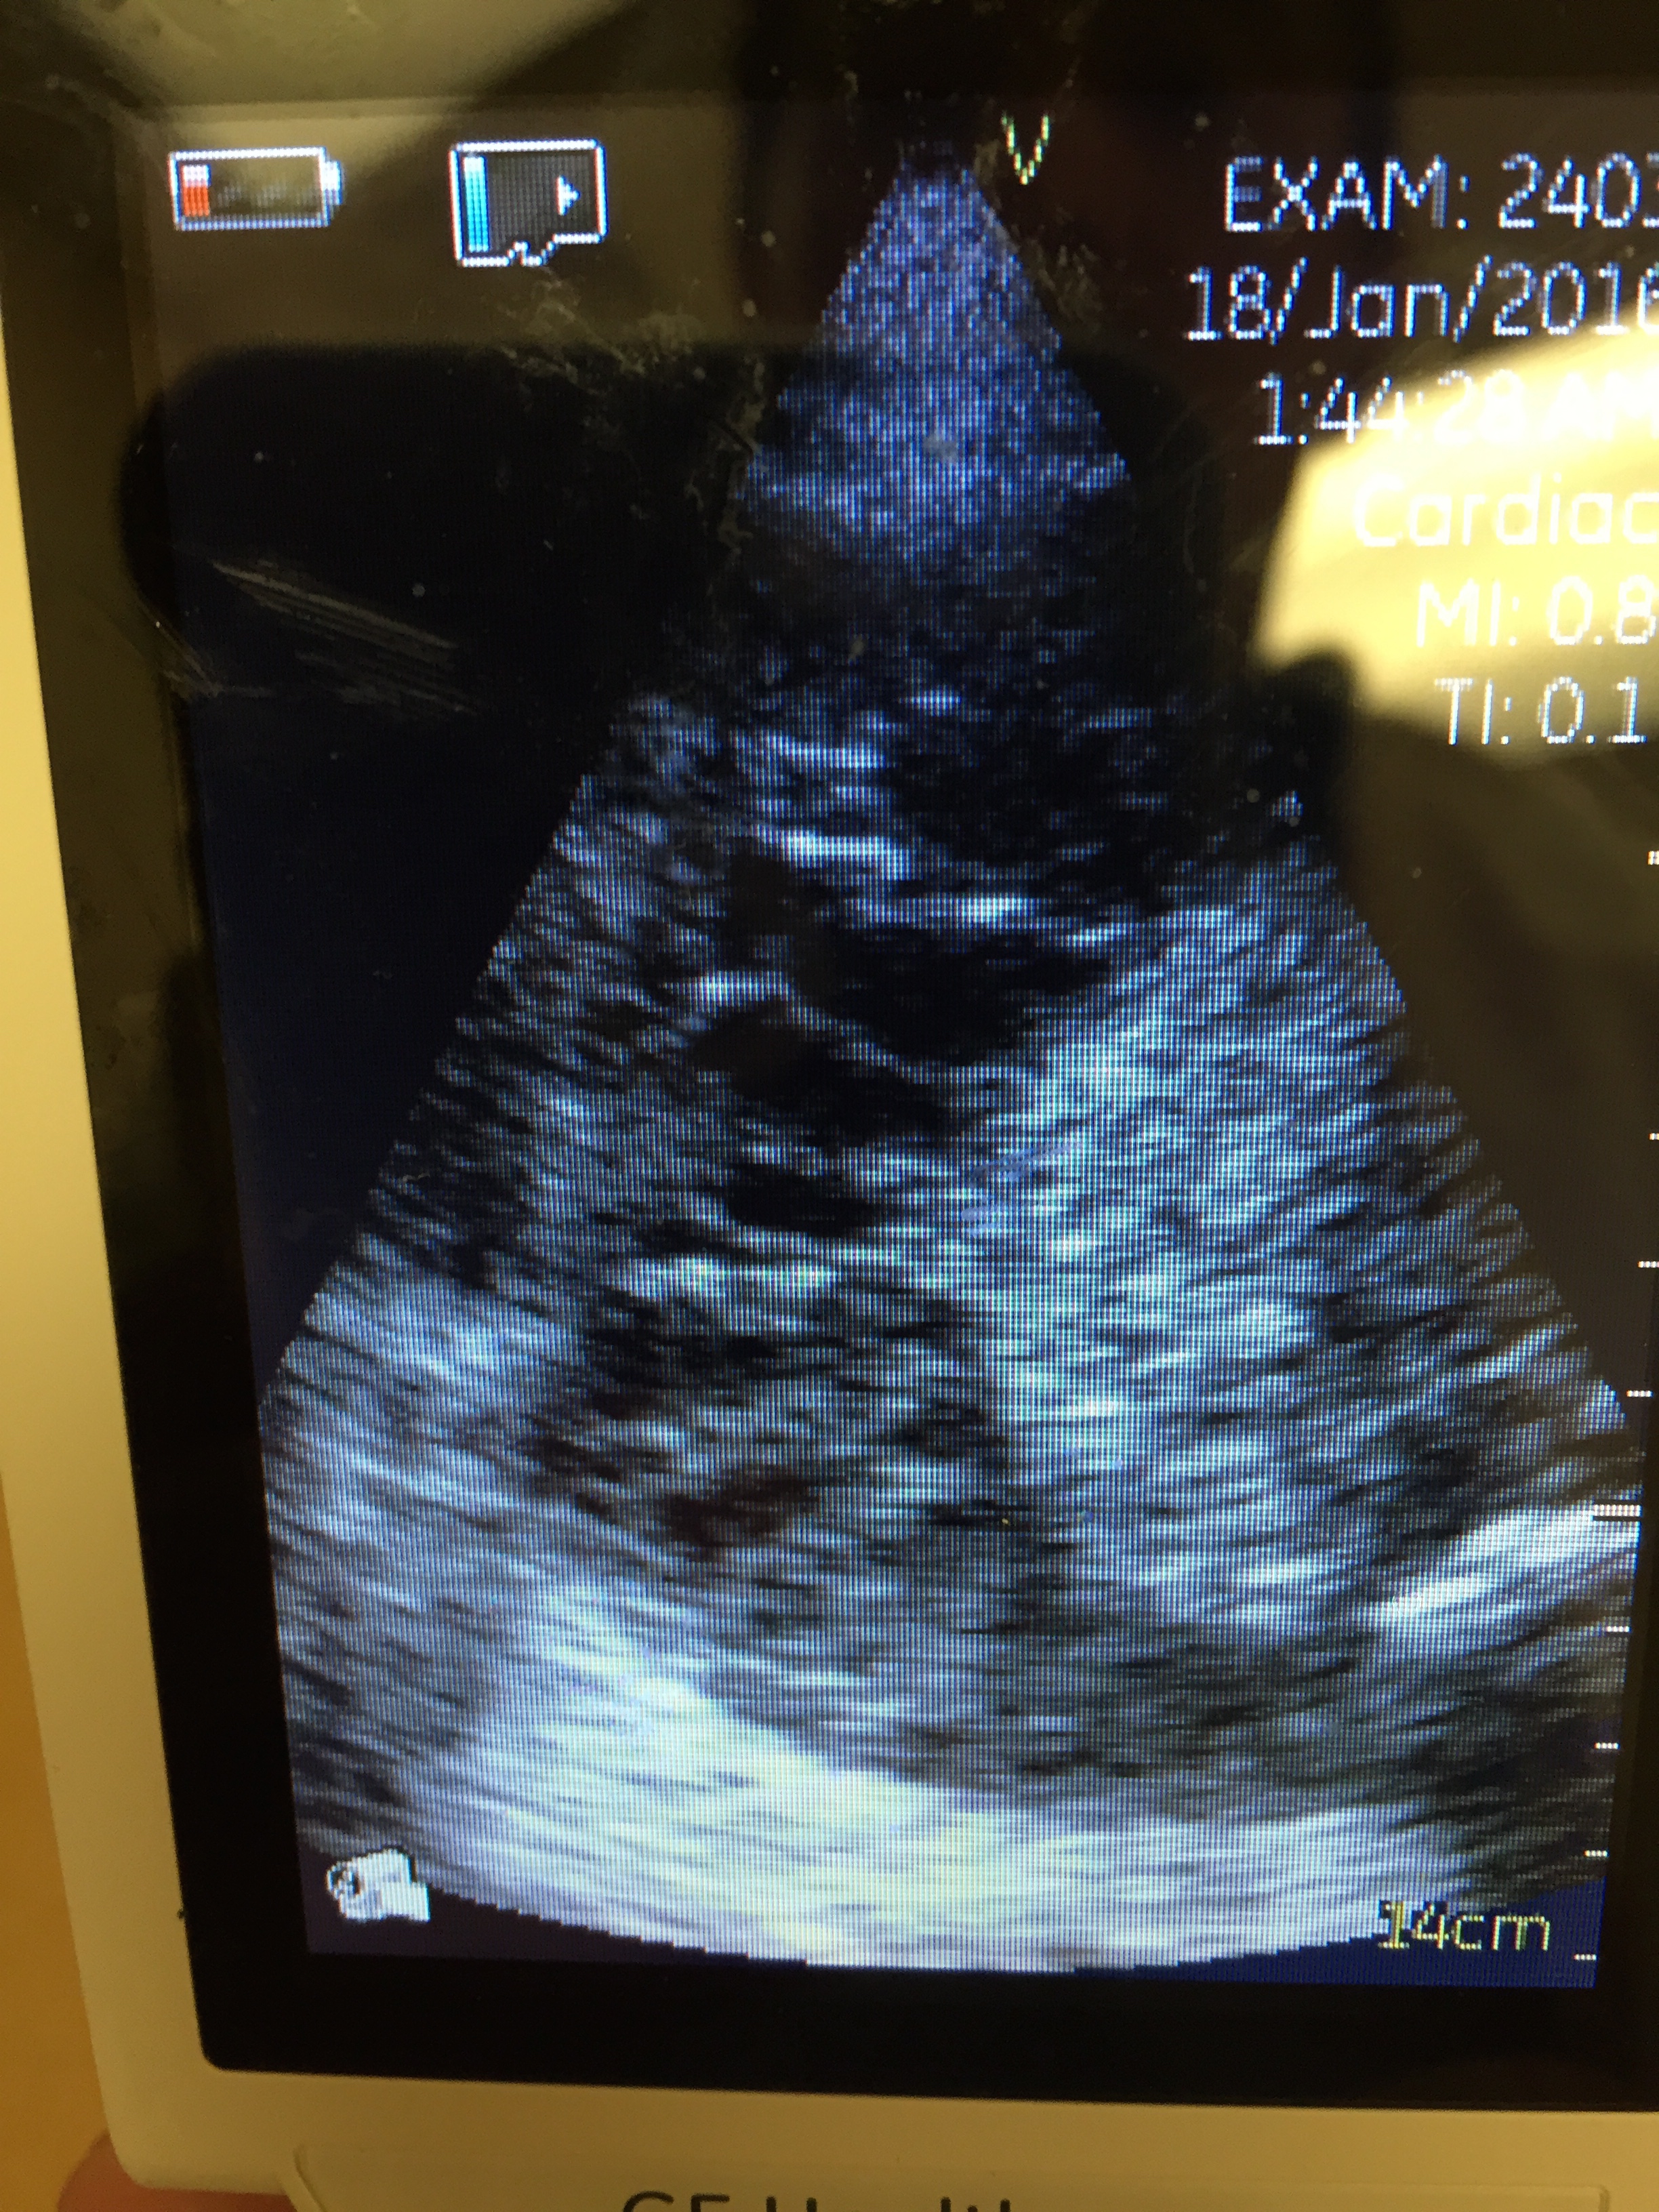

So of course we had to pick up the probe and take a look:

So the optic nerves are dilated significantly (bilaterally), suggesting an ICP over 20 mmhm at the very least.